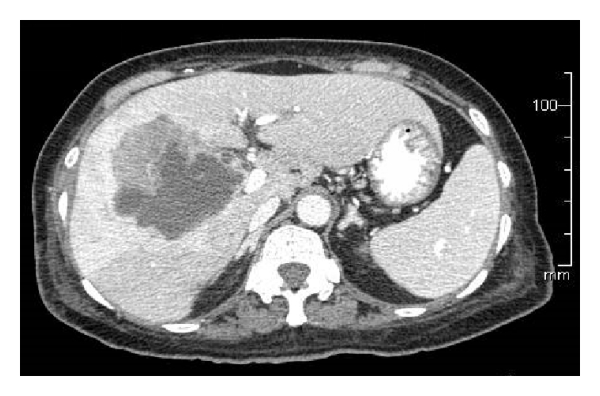

A 67-year-old Asian female presented to her primary care physician in March 2012 with persistent fever and chills with associated weakness and weight loss. She had no abdominal symptoms or history of gallbladder pathology. She was treated for bronchitis but her fever and chills persisted despite multiple rounds of oral antibiotic therapy. Further workup revealed a leukocytosis of 30,000 wbc/μL. She underwent hematology/oncology evaluation to exclude a possible bone marrow dysplastic process. This did not demonstrate an underlying cause for the leukocytosis. She presented to a local emergency room in mid-June 2012 with complaints of chills, weakness, and malaise. She was admitted with Gram-negative rod bacteremia. A computed tomography (CT) scan was obtained which demonstrated an 8.6 cm mass of the right lobe of the liver with associated abscess (Figure 1). Biopsy of the lesion revealed SCC of the gallbladder (Figure 2). Percutaneous drainage of the abscess was performed which was significant for E. coli and Enterococcus. She was discharged on antibiotic therapy but readmitted ten days later with fever, chills, and failure to thrive. Repeat CT scan imaging revealed an increase in the size of the mass to 10.2 cm. Evidence of fistulization of the lesion to the gastric antrum, duodenum, and hepatic flexure of the colon was also noted (Figures 3 and 4). There was no distant metastasis or lymphadenopathy observed. She was referred to our institution in August 2012 for consideration of additional therapy. Magnetic resonance imaging revealed her tumor to be potentially resectable. However, because of her limited reserve and declining functional status, it was felt that she may not tolerate radical en bloc resection. Palliative chemotherapy was offered but declined. Comfort care measures were recommended and the patient passed away soon thereafter.